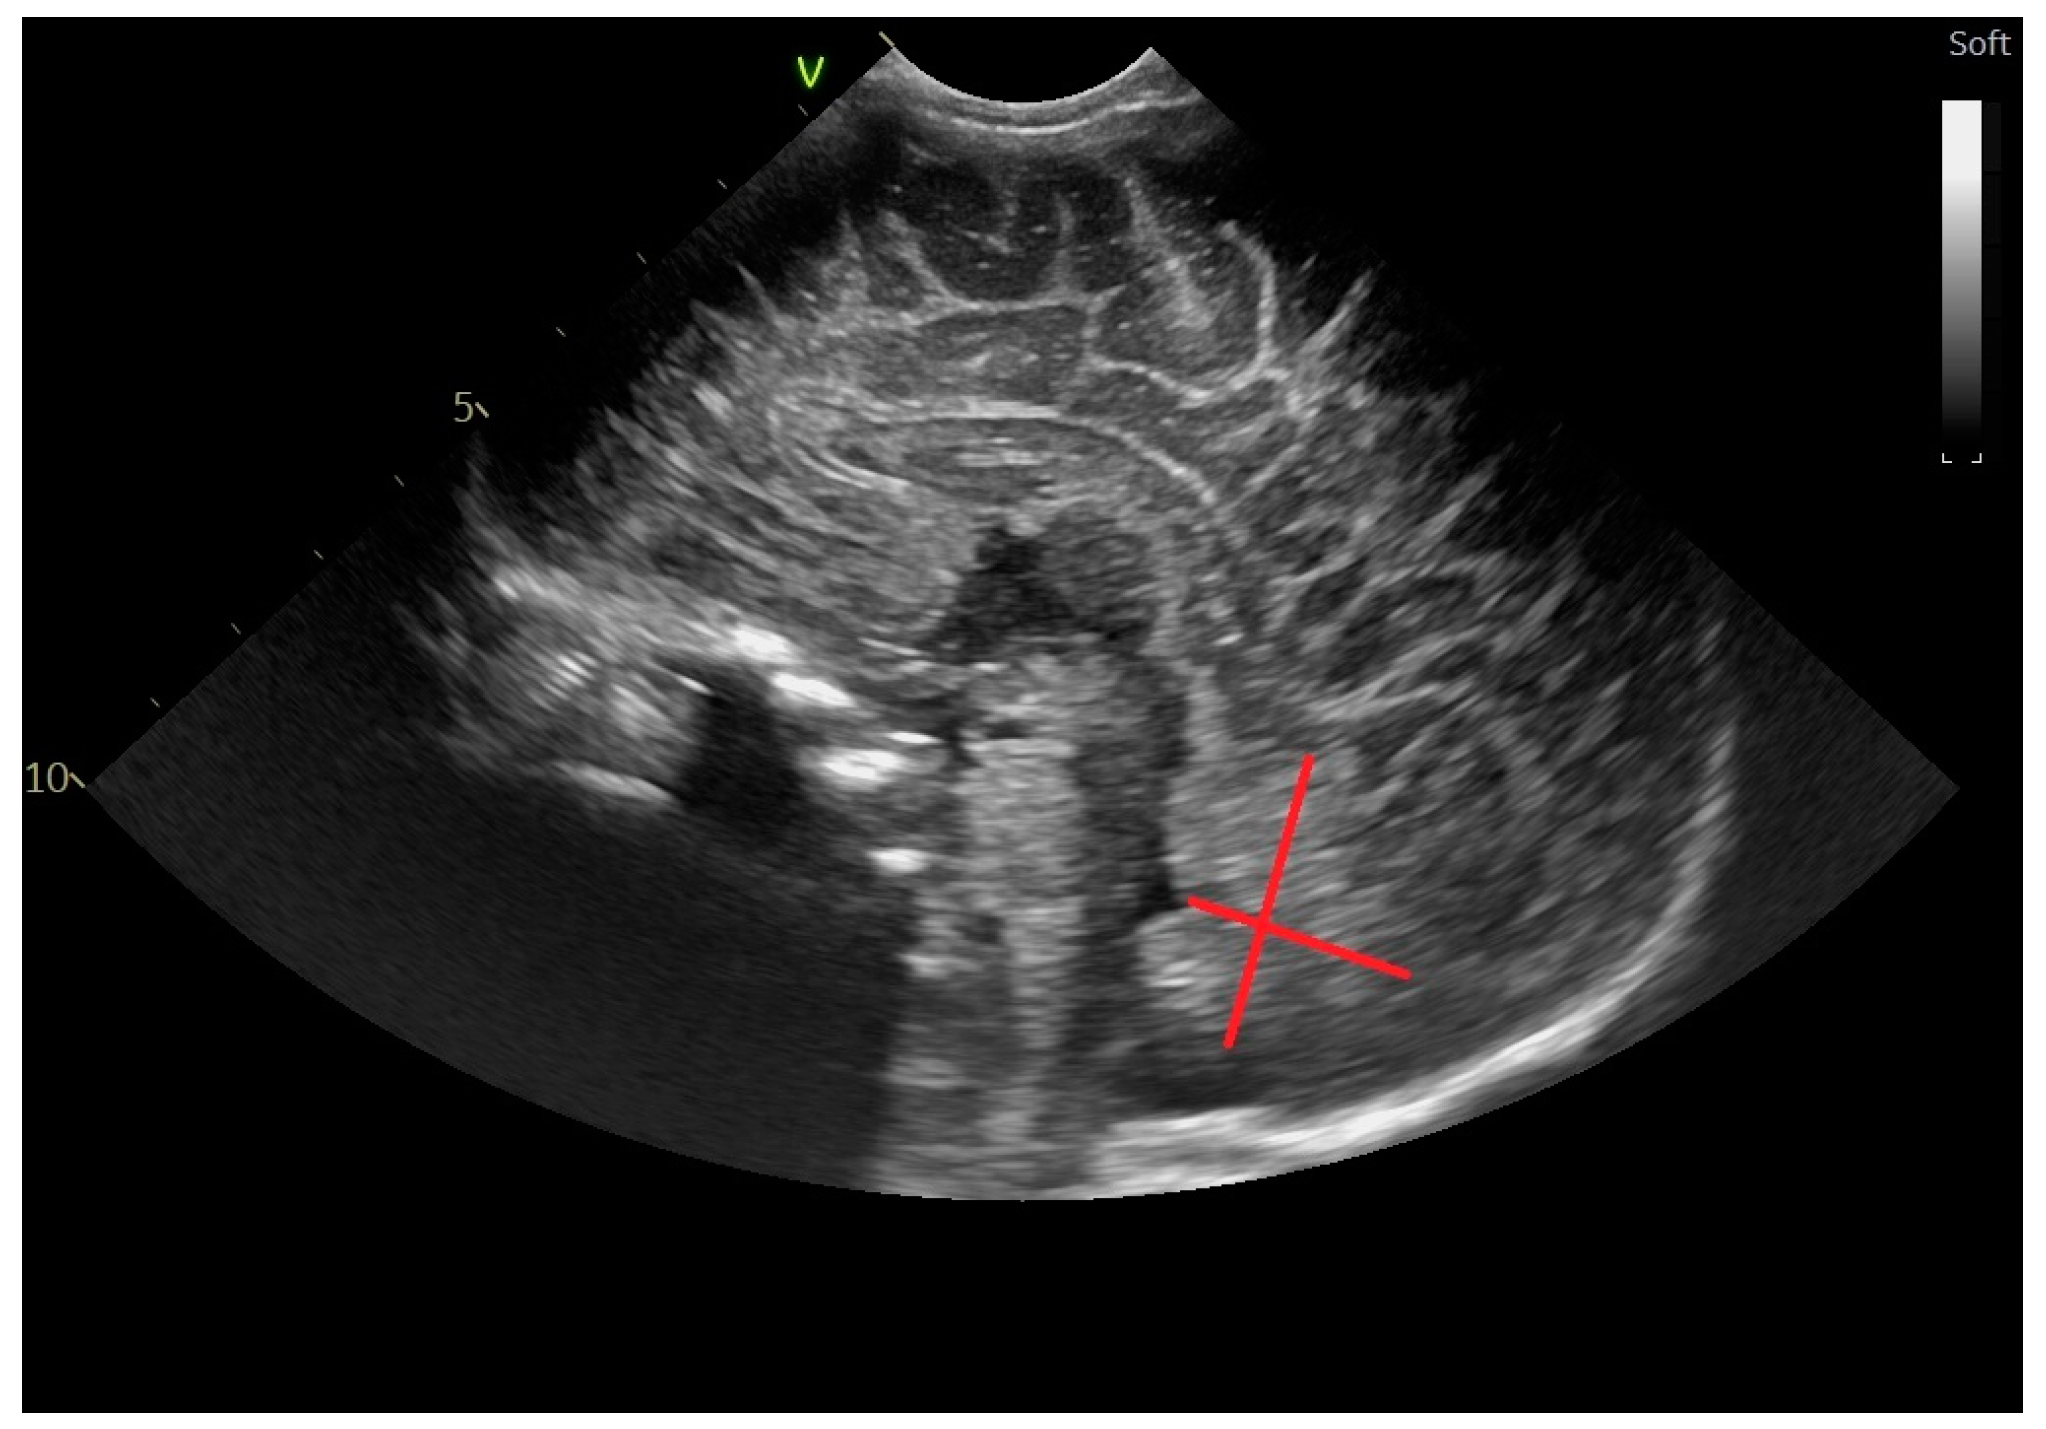

2.2. Head Ultrasound Measurements at TEA